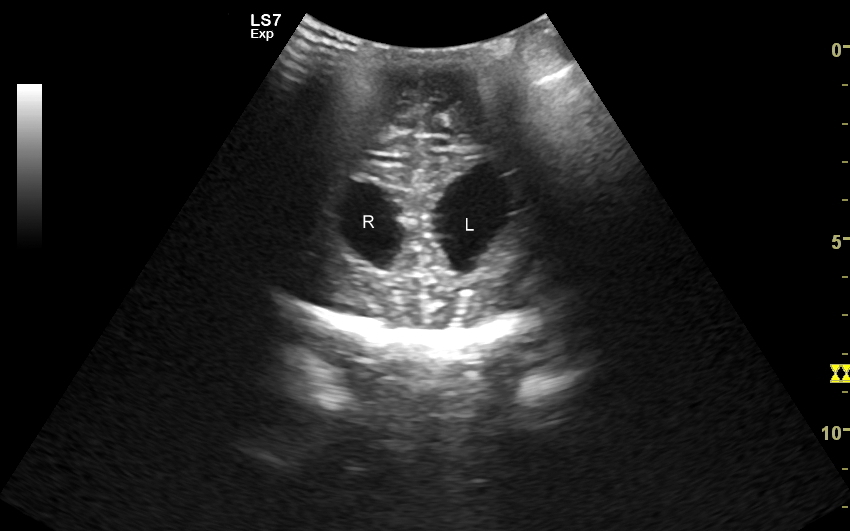

USG główki z oceną szwów i powłok

Poza strukturami wewnątrzczaszkowymi w badaniu USG główki niemowlaka oceniana jest pokrywa czaszki, w tym szwy i kości czaszkowe, tkanka podskórna oraz skóra głowy. Badanie USG szwów czaszkowych ma istotne znaczenie przy ocenie niesymetrycznego lub zdeformowanego kształtu głowy w kontekście rozpoznania kraniosynostozy (ang. craniosynostosis), tj. stanu, w którym dochodzi do przedwczesnego oraz nieprawidłowego zarastania szwów. W kraniosynostozie w miejscu zarastania tworzy się zwykle patologiczne twarde uwypuklenie / guz, które posiada charakterystyczny obraz sonograficzny pozwalający na rozróżnienie zarastania szwów w przebiegu kraniosynostozy od przedawkowania witaminy D, czy fizjologicznej wcześniejszej fuzji kości czaszki.

Patologiczne zarastanie szwów może być symetryczne lub niesymetryczne oraz dotyczyć jednego lub więcej szwów. W zależności od tejże konstelacji czaszka może przyjmować różnorodne formy deformacji w postaci scaphocefalii (syn. dolichocephalia, czaszka łódkowata / wydłużona w przebiegu zarośnięcia szwu strzałkowego), brachycefalii (krótkogłowie w przebiegu zarośnięcia obu szwów wieńcowych)trigonocefalii (trójkątnogłowie w przebiegu zarośnięcia szwu czołowego), plagiocefalii przedniej lub tylnej (skośnogłowie w przebiegu zarośnięcia jednego ze szwów wieńcowego lub węgłowego), turricefalii (syn. oxycefalia, czaszka wieżowata w przebiegu zarośnięcia szwów wieńcowych i któregoś z pozostałych), mikrocefalii (mała czaszka w przebiegu zarośnięcia wszystkich szwów) lub czaszki w kształcie liścia koniczyny (niem. kleeblattschädel). Sprawna diagnostyka deformacji czaszki ma wielkie znaczenie. Otóż kraniosynostoza jest potencjalnie niebezpieczna dla zdrowia, a nawet życia dziecka, a zwykle leczy się ją chirurgicznie. Z kolei częściej występująca łagodna deformacja w postaci plagiocefalii ułożeniowej wywołana jest zwykle tendencją do leżenia dziecka na wznak z główką skierowaną w jedną stronę, zwykle prawą; jest ona problemem bardziej estetycznymi aniżeli medycznym, a leczy się ją przy pomocy kasku oraz zaleceń rehabilitacyjnych.